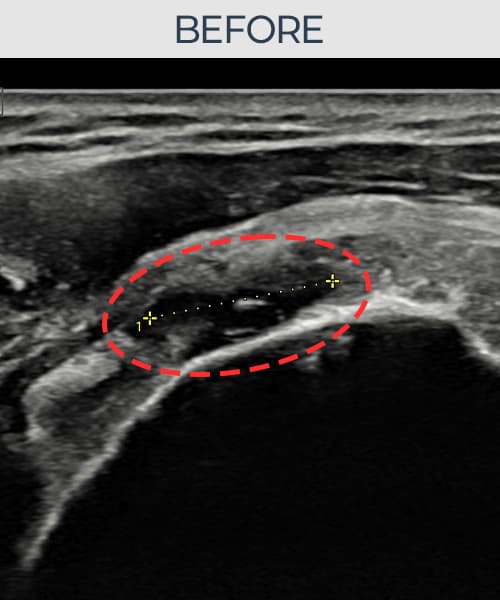

右侧 冈上肌腱 石灰化肌腱炎

14mm × 10mm